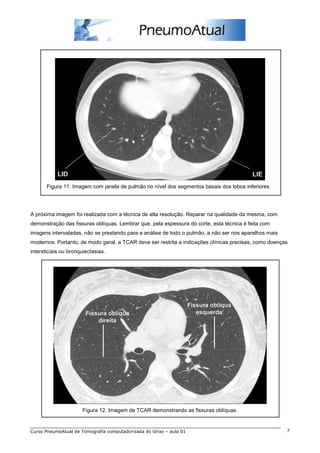

Figura 11. Imagem com janela de pulmão no nível dos segmentos basais dos lobos inferiores.

A próxima imagem foi realizada com a técnica de alta resolução. Reparar na qualidade da mesma, com

demonstração das fissuras oblíquas. Lembrar que, pela espessura do corte, esta técnica é feita com

imagens intervaladas, não se prestando para a análise de todo o pulmão, a não ser nos aparelhos mais

modernos. Portanto, de modo geral, a TCAR deve ser restrita a indicações clínicas precisas, como doenças

intersticiais ou bronquiectasias.

Figura 12. Imagem de TCAR demonstrando as fissuras oblíquas.

Figura 11. Imagemcom janela de pulmão no nível dos segmentos basais dos lobos inferiores. A próxima imagem foi realizada com a técnica de alta resolução. Reparar na qualidade da mesma, com demonstração das fissuras oblíquas. Lembrar que, pela espessura do corte, esta técnica é feita com imagens intervaladas, não se prestando para a análise de todo o pulmão, a não ser nos aparelhos mais modernos. Portanto, de modo geral, a TCAR deve ser restrita a indicações clínicas precisas, como doenças intersticiais ou bronquiectasias. Figura 12. Imagem de TCAR demonstrando as fissuras oblíquas. Curso PneumoAtual de Tomografia computadorizada do tórax – aula 01 7